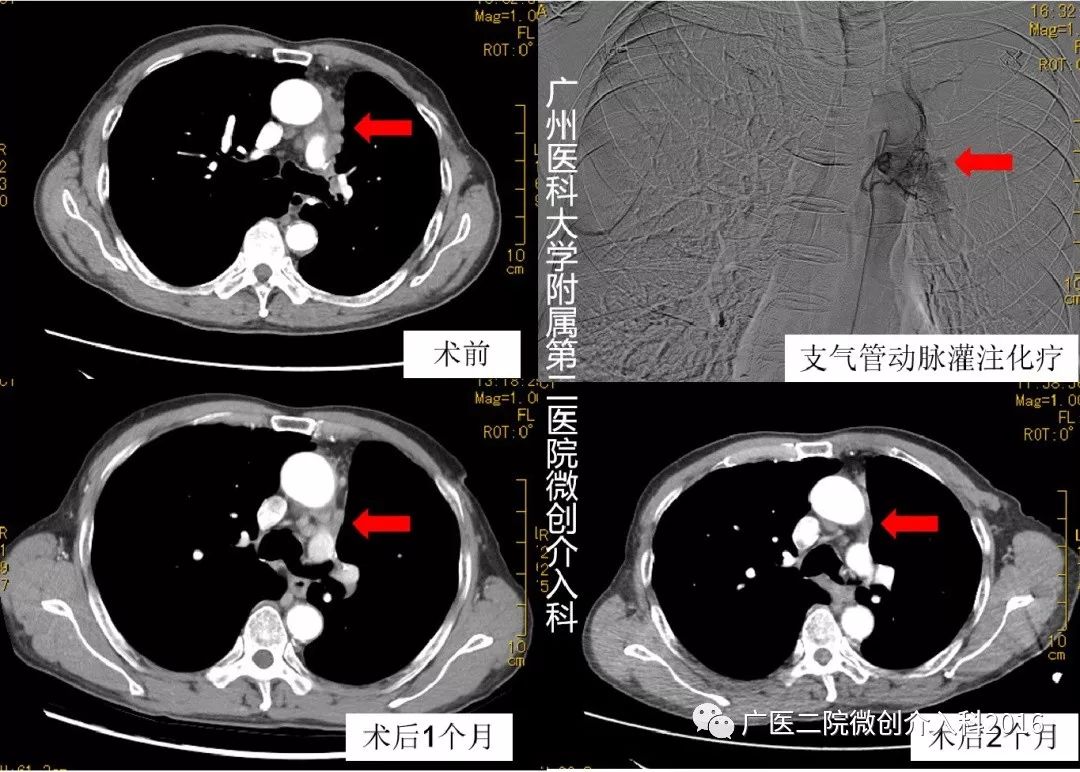

男性,79岁,复合性大细胞神经内分泌癌(复合成分低分化鳞状细胞癌)切除术后2年余,复查发现纵膈、肺门淋巴结多发转移, 在外院行多次全身静脉化疗无效。入院后基因检测提示:无基因突变、无靶向药物可用,该患者检测TMB 4.6个突变/Mb。在我科行2次支气管动脉灌注化疗➕PD1免疫治疗,术后2个月复查纵膈、肺门淋巴结转移病灶基本消失,疗效显著!

专家点评

该患者为神经内分泌癌,恶性程度高,预后差。该患者经过基因检测无基因突变,无靶向药物可用。虽然TMB不高,但在支气管动脉灌注化疗治疗的基础上,治疗有助于激活肿瘤特异性免疫系统,联合PD-1免疫治疗取得了良好疗效。局部化疗联合免疫治疗的远期疗效值得期待!